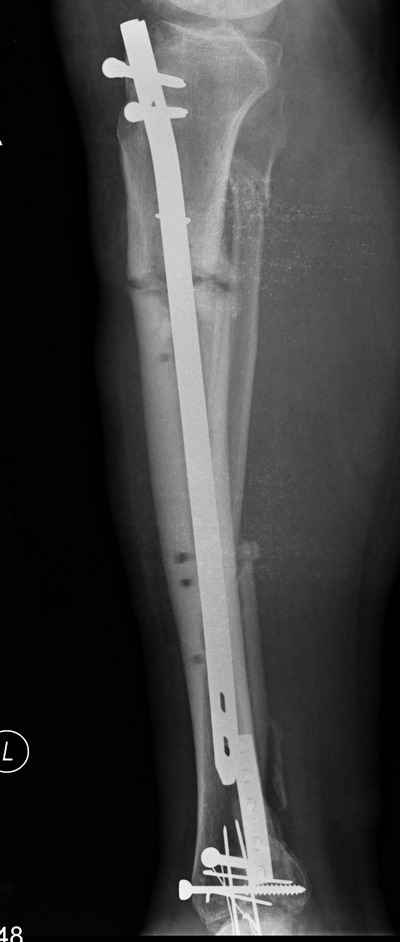

2. С аппаратом и резекцией малоберцовой кости все понятно, но почему вы предполагаете значимое укорочение, требующее транспорта? В моем случае есть признаки формирования нормотрофического (по крайней мере не аваскулярного несращения)- в приложении боковая рентгенограмма.